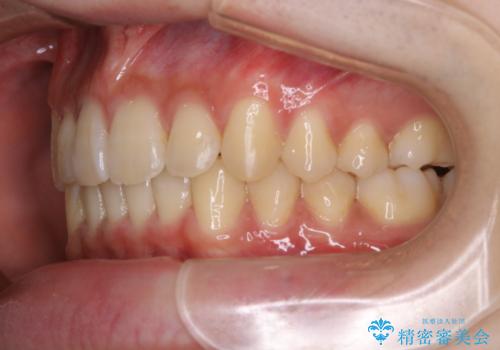

- 前歯のがたつきが気になるとご相談にいらした方です。左の奥歯の噛み合わせのズレも認められたため、インビザライン治療にて改善しました。

主訴である前歯のガタつきだけでなく、奥歯の噛み合わせからしっかり治療したため、治療期間が長めとなりました。患者様ご本人としては治療の途中で一時的にモチベーションが下がったこともあったようですが、最後まで頑張って続けて頂けたことで噛み合わせ及び見た目の改善を行うことが出来ました。